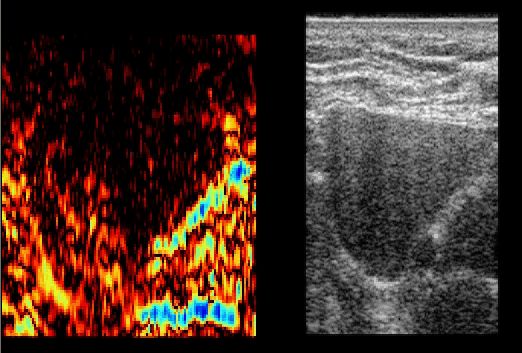

Echtzeit Elastographie: in vivo Leber Sample 01 (gif)

Echtzeit Elastographie: in vivo Leber Sample 02 (gif)